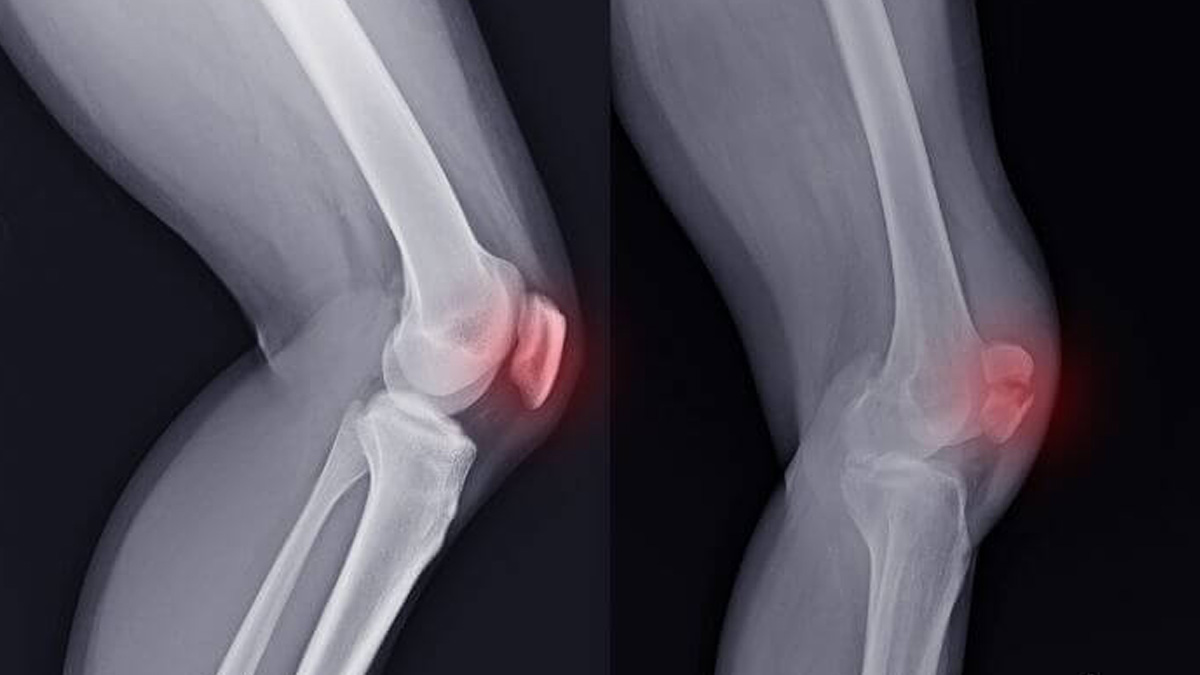

To understand the injury better, we spoke to Dr Siddharth Gupta, who explains that healing without surgery depends on the injury’s severity. “Yes, in certain situations, a dislocated knee heals on its own, but it depends heavily on the extent of injury and structures involved,” says Dr Gupta. “A knee dislocation happens when bones like the femur and tibia get displaced from their proper position, usually due to trauma such as falls or sports injuries.”

In cases where ligament, nerve, or blood vessel damage is minimal, doctors may attempt a closed reduction, the manual realignment of the knee bones, followed by immobilisation. “The knee is then braced or splinted to allow soft tissues to heal. Physical therapy is crucial to regain strength, flexibility, and motion,” adds Dr Gupta.

However, many knee dislocations involve torn ligaments, especially the ACL, PCL, and collateral ligaments. “If multiple ligaments are torn, or there is nerve or blood vessel involvement, surgery is necessary to repair or reconstruct damaged tissues and restore joint stability,” Dr Gupta says.